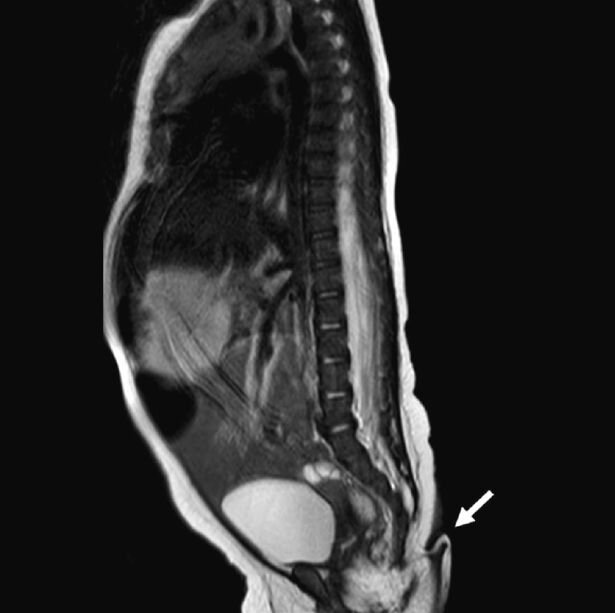

متخصصان پزشکی برای طیف وسیعی از مشکلات پزشکی آزمایش انجام دادند و مشخص شد که هیچکدام از آنها وجود ندارد. اسکن MRI نیز هیچ ناهنجاری مغزی را نشان نداد و برای ناهنجاری های ستون فقرات نیز نتیجه منفی بود.